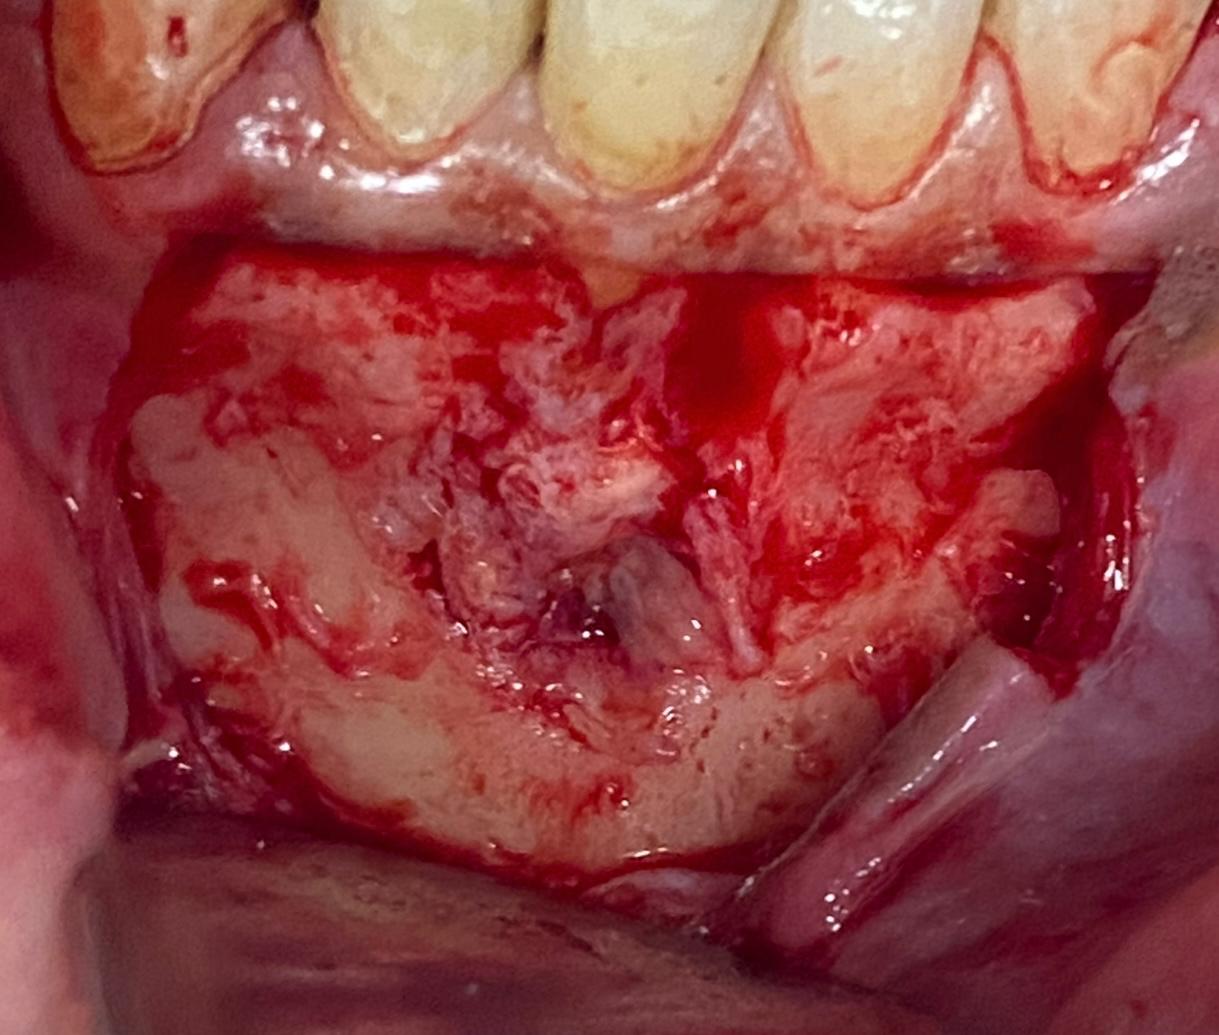

Se le realiza un TAC donde se observa una imagen radio lúcida de 11,3 mm de ancho y 8,5 mm de largo Esta imagen es compatible con un quiste odontogenico del 41 posiblemente causado por un fracaso endodontico. La imagen radiográfica afecta también al 42 pero dicho diente está vital. Se realiza un colgajo para hacer la quistectomía y apiceptomía del 41. Se regenera con hueso autólogo: xenoinjerto en una proporción 70:30 y membrana de colágeno STD de media reabsorción.

Los procesos quísticos de gran tamaño, pueden ser resueltos mediante la extracción del diente y extirpación del quiste. En este caso el hueso remanente hubiera sido insuficiente para posteriormente poner un implante, asique se decide hacer quistectomía y regeneración ósea guiada del defecto óseo